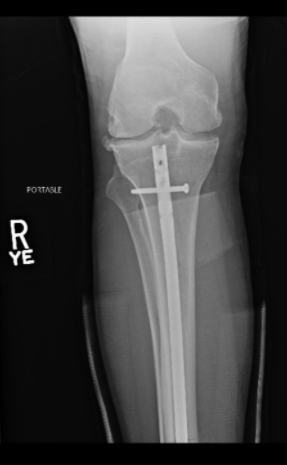

A través de su cuenta de Twitter, el artista marcial compartió imágenes del proceso que se llevó a cabo para reconstruir su pierna. En ellas se pueden ver la barra de titanio que se le dejó para afirmar sus huesos, además de los tres tornillos que fijaron la placa.

Luego de la intervención. Foto: Twitter